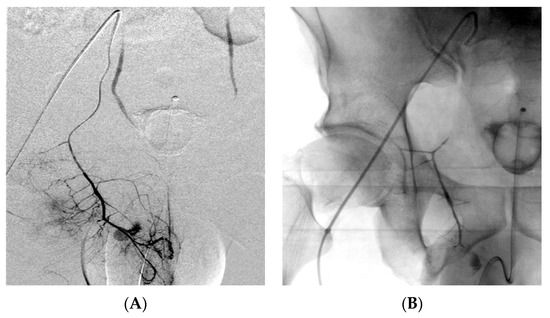

| Site of bleeding - Pelvic - Upper GI - Lower GI - Abdomen - Thorax - Neck - Limbs | 15 (28.4%) 4 (7.5%) 2 (3.8%) 18 (34%) 8 (15%) 2 (3.8%) 4 (7.5%) |

| Cause of bleeding - Trauma - Spontaneous - Others (tumors, diverticula, ulcers, etc.) | 31 (58.5%) 5 (9.4%) 16 (32.1%) |